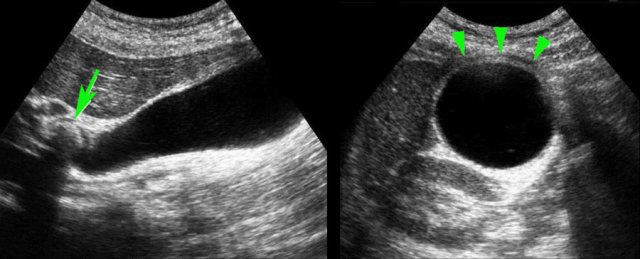

Even in the case, when there is intervening liver tissue between the abdominal wall and the gallbladder, an indirect “hydrops-sign” can be demonstrated.

The left image shows a gallbladder that keeps its rounded shape, without and during compression, and bulges into the soft interposing liver tissue and abdominal wall.

Likewise, the absence of hydrops can be demonstrated, even when there is intervening liver tissue, which is soft during compression (image on the right).

Here two examples of impacted stone visualized during biliary colic in different patients.

In the supine position a stone (arrow) is demonstrated in the gallbladder neck.

After standing up, bending over and walking, the stone (arrow) does not fall down, and therefore must be impacted.

Stones in the cystic duct are sometimes not demonstrable in the US plane of the longitudinal axis of the gallbladder.

Here images of a patieny with acute hydrops due to an impacted stone.

The impacted stone could not be visualized in the longitudinal axis of the gallbladder, due to its medial position in the cystic duct (arrow).